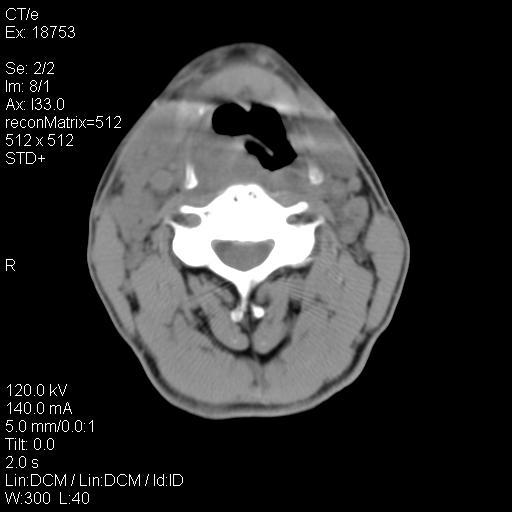

标题: CT21693:男 58岁 右侧咽部疼她2天余 PE:右侧扁桃体肿大 压痛 [打印本页]

标题: CT21693:男 58岁 右侧咽部疼她2天余 PE:右侧扁桃体肿大 压痛

右化脓性扁桃体炎症伴咽后壁脓肿形成.

喉部新生物,喉癌可能大,建议喉镜取组织活检。

考虑感染性病变可能性大,建议抗炎治疗后复查,必要时鼻咽腔镜活检排除占位。